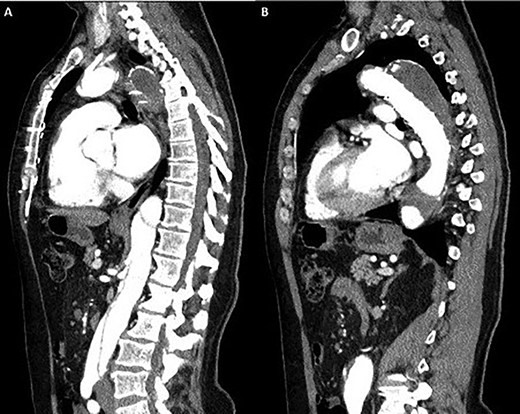

Coronal section CT scan images demonstrating the newly arranged epiaortic reconfiguration on left (A) and on the right (B) the deployed FET and antegrade flow in the descending thoracic aorta through the true lumen.

Cardiopulmonary bypass support was established using right atrial drainage and right axillary artery return. During cooling to 18°C, the aorta and epiaortic arch vessels were mobilized and encircled with tapes. At 21°C, the heart was fibrillated, aortic cross-clamp applied and antegrade cold blood intermittent cardioplegia administered to arrest the heart. At 18°C, neuroprotective protocol (topical ice to the head, intravenous steroids and mannitol administration with near infrared spectroscopy monitoring of cerebral saturations) was instituted and circulatory arrest commenced. The ascending aorta was transected 1 cm proximal to innominate artery and aortic arch inspected. Selective antegade cerebral perfusion was commenced. The aortic arch was divided in Zone 2 in order to protect the recurrent laryngeal nerve. The origin of the aberrant left vertebral artery and left subclavian artery were oversewn with a running 4/0 prolene suture. A 30/32/150 mm Thoraflex stent graft was deployed into the true lumen of the descending aorta. The cuff on the stent graft was anastomosed to the distal arch. Attention was then directed to the left common carotid and innominate arteries that were fashioned and anastomosed to the corresponding grafts on the stent graft. The aortic cross clamp was applied on the ascending aorta portion of the stent graft and total body circulation and rewarming was reinstituted. The ascending aorta was anastomosed to the stent graft 1 cm proximal to the innominate artery. A thorough de-airing drill was undertaken, the aortic cross clamp released and heart perfused. The graft on stent graft corresponding to the left subclavian artery was anastomosed and the origin on the aortic arch was oversewn. A 6-mm Dacron graft was then anastomosed to the transected left vertebral artery and origin on the aortic arch oversewn. The 6-mm Dacron graft was then anastomosed to the 8-mm side arm on stent graft corresponding to the perfusion arm. When fully rewarmed, cardiopulmonary bypass support was successfully weaned off and patient was in sinus rhythm requiring no inotropic support. Postoperatively, the patient made an uneventful recovery and was subsequently discharged home without complications and seen in the outpatient clinic as part of their routine surveillance. Computed tomography (CT) imaging performed as an outpatient demonstrated normal graft appearances, aortic arch and epiaortic vessel configurations (Fig. 3).